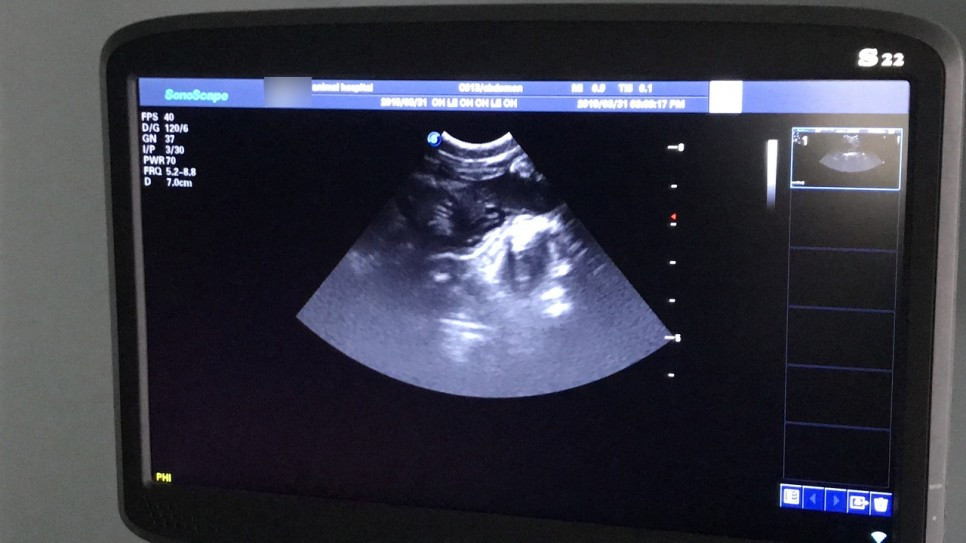

수의사 선생님과 면담을 했다. 우선은 초음파로 임신 여부를 확인해야 하는데, 임신 20일 이전의 초기 상태에서는 초음파로도 임신 여부가 확인되지 않는다고 한다. 하지만 친구에게 듣기론 레오의 배에 아기가 움직이는 게 육안상으로 보일 정도라고 했으니 초기는 아닐 것 같아 진행하기로 했다.

사나운 레오의 정신이 돌아왔으니 초음파를 진행하는 동안 화를 낼 거라고 생각했는데, 의외로 레오는 아주 얌전히 있어주었다. 정신만 돌아오고 기력은 돌아오지 않은 탓일까? 하지만 레오의 눈빛은 '이 인간들이 나를 도와주려는구나' 하고 이해하는 얼굴이었다.

초음파로 확인한 결과 레오는 임신이 맞았다. 아기 심장이 뛰는 것을 내 눈으로 직접 확인했다. 감격스럽고도 원망스러운, 대견하고도 안쓰러운 오묘한 감정이 들었다. 마릿수는 꽤 많아 보이는데, 정확한 마릿수는 초음파가 아닌 X-ray로 확인해야 한다고 한다. X-ray는 44,000원이었고 찍지 않았다. 가격 때문이 아니라 순간적으로 방사능이 걱정되어 한 선택이었는데, 집에 와서 '찍을걸, 찍어볼걸.'하고 매우 후회했다.